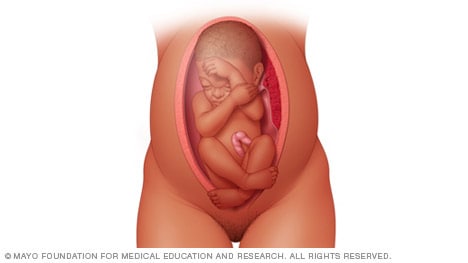

Frank breech

When a baby’s feet or buttocks are in place to come out first during birth, it’s called a breech presentation. This happens in about 3% to 4% of babies close to the time of birth. The baby shown below is in a frank breech presentation. That’s when the knees aren’t bent, and the feet are close to the baby’s head. This is the most common type of breech presentation.

If you are more than 36 weeks into your pregnancy and your baby is in a frank breech presentation, your health care professional may try to move the baby into a head-down position. This is done using a procedure called external cephalic version. It involves one or two members of the health care team putting pressure on your belly with their hands to get the baby to roll into a head-down position.

If the procedure isn’t successful, or if the baby moves back into a breech position, talk with a member of your health care team about the choices you have for delivery. Most babies in a frank breech position are born by planned C-section.